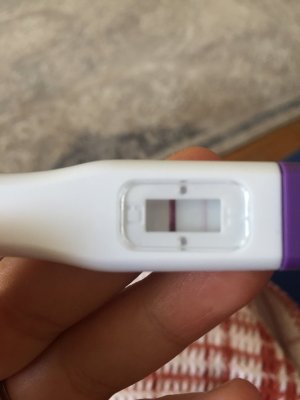

Merhaba kızlar ben reglme 2 gün kala erken gebelik testi yaptım silik çizgi çıktı snra emin olmak için bir tane daha yaptım oda silik cıktı bu gun regl gunum olmadım gittim normal gecelik testi yaptım onda da çok silik çizgi cıktı sizdn fikir almak istiyorum sizce var mı testleri buraya koycam karartma yaptım

Erken gebelik testi